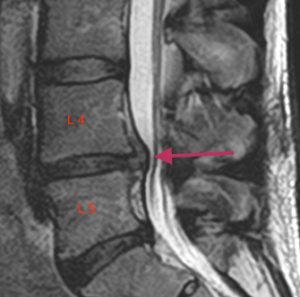

Lannerangan magneettikuva 1

Lannerangan sivuprofiili (sagittaalikuva).